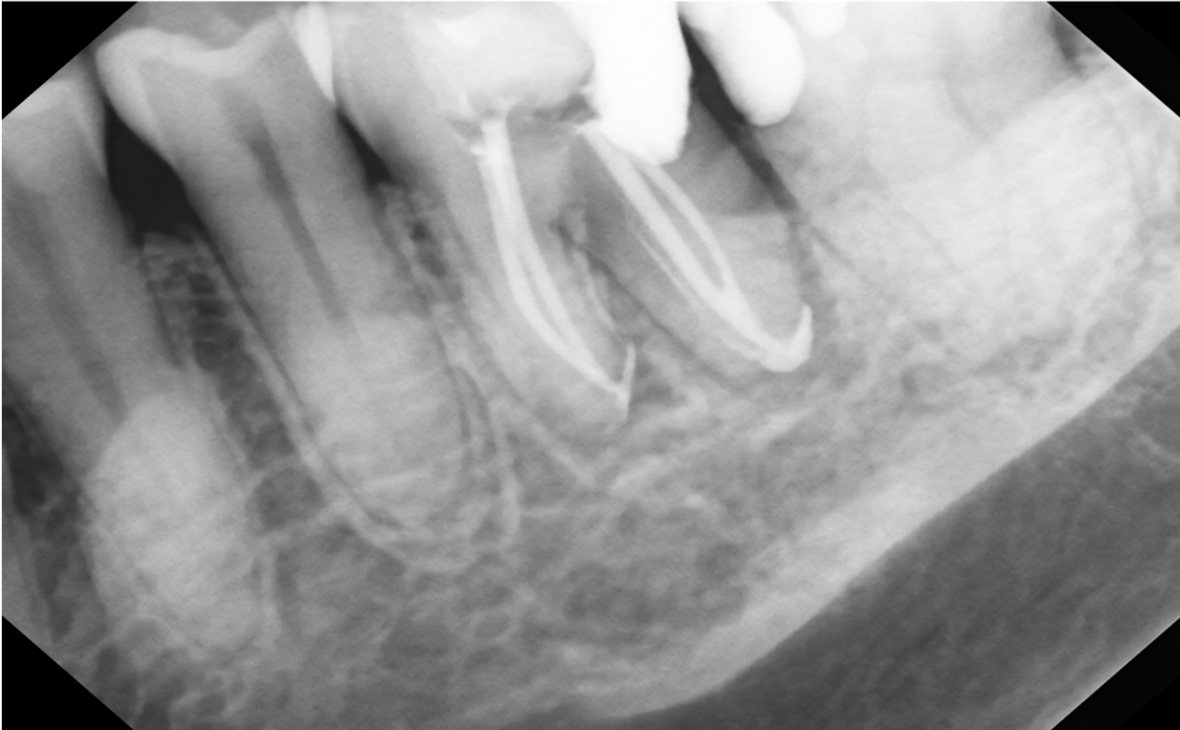

Working Length Determination

Case #10

A 14 year old female presented with parents for root canal treatment # 29. She had her braces removed recently and noticed a large, buccal swelling.

# 29 (+)perc, (+)palp, buccal swelling, no response to cold, (+)periapical lesion

#29

Apical: acute apical abcess

Pulpal: necrotic

Pre Op #29

Treatment was completed in two visits. The goal of the first visit was to get the patient out of pain, I slightly instrumented and irrigated the canal; I placed calcium hydroxide and temporized with cotton pellet and cavit.

On the 2nd visit, she came back two weeks later, her swelling was gone and she was feeling better. We finished the case and the patient was very happy.

The interesting factor was that apex was open and the tooth was necrotic. These are sometimes hard to manage because we don’t want to push our filling materials past the apex. I performed a procedure where I placed 3 mm of BC putty apically and then filled the rest of the canal with bioceramic sealer and Gutta Percha. I was happy that the material was contained and wasn’t pushed outside the apical segment. In order to contain the material, I always take a radiograph with a file and obtain my working length